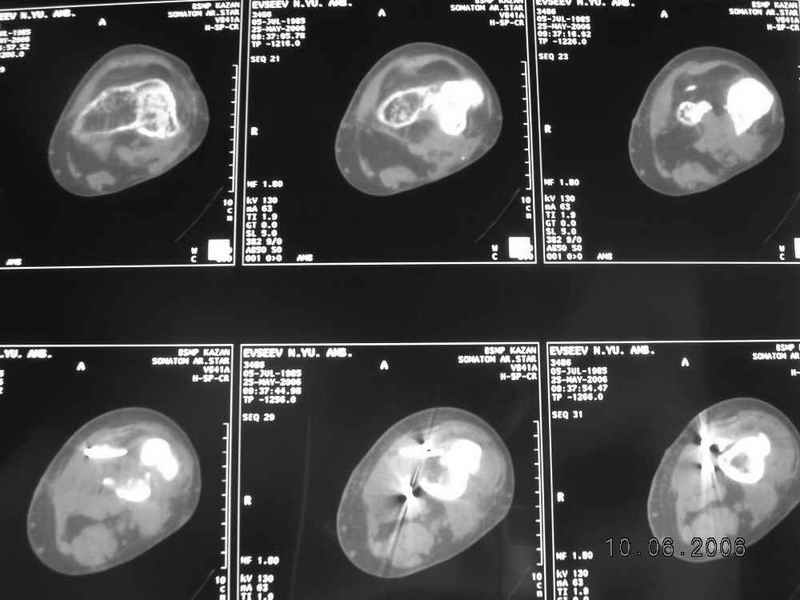

Рефрактур уж точно можно будет не опасаться, а за несколько месяцев даже при отсутствии заполнения костью по всей окружности, этот обходной "мостик" упрочнится и возьмет на себя нагрузку. В приложении пример такого рода "эндопротезирования диафиза", прошло больше 3 лет.

Пациентка, страдающая еще и инсулинозависимым диабетом, не хромает, работает инженером.